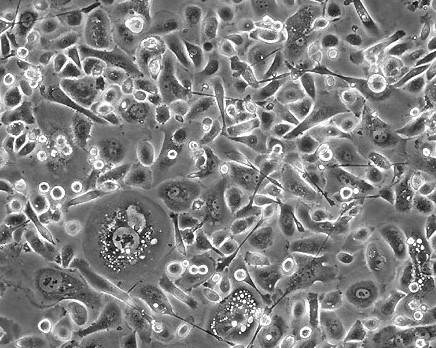

PC-3

PC3; PC.3

90%Ham's F-12K+10% FBS

Temperature: 37°C ; Carbon dioxide (CO₂), 5%

贴壁细胞